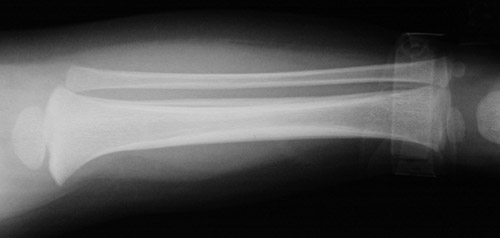

This radiograph of the lower leg demonstrates extensive periosteal new bone from an old healing fracture of the tibia in an infant. The appearance of other fractures of varying ages in this child raised suspicion for child abuse.